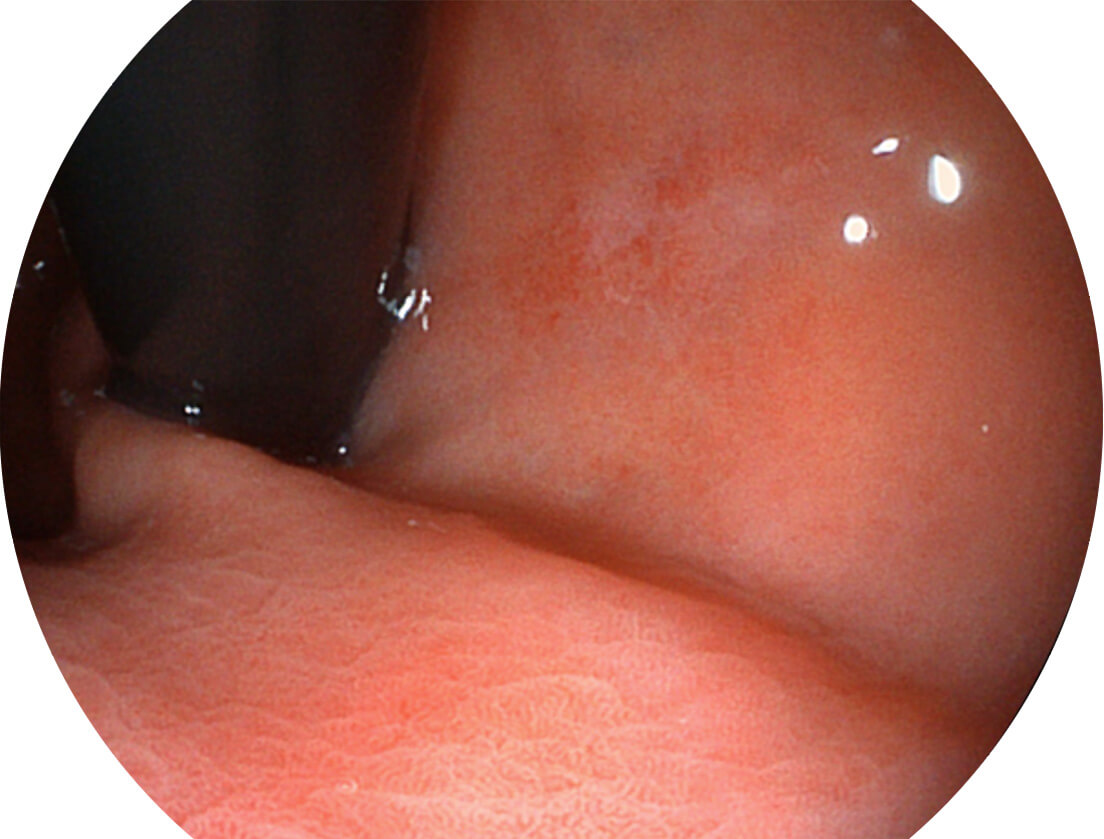

SFI图像

白光图像

VIST图像